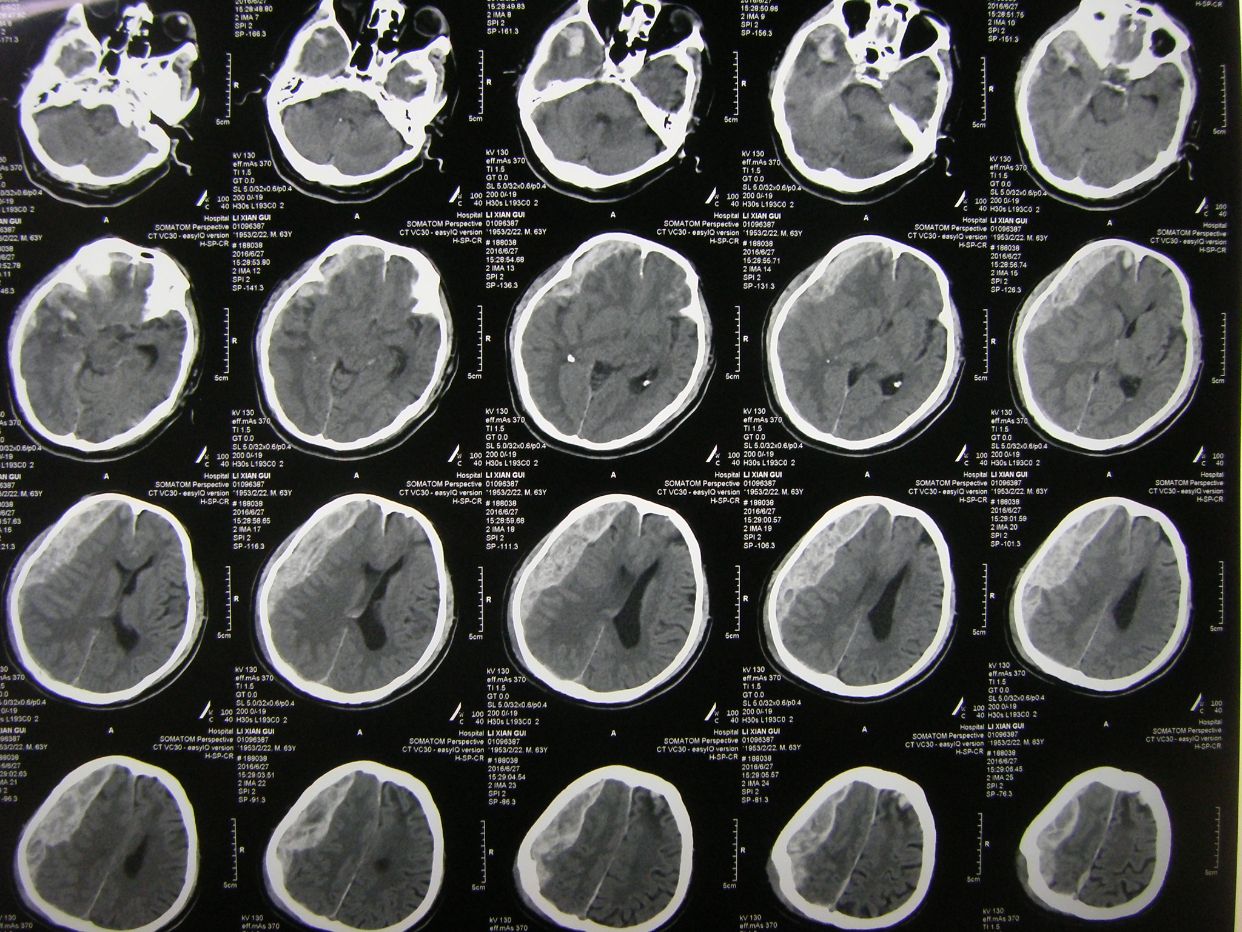

例2,男,63岁,被发现卧倒在地意识不清半小时入院。

CT示右额颞顶大量硬膜下血肿,右额颞叶脑挫裂伤,中线明显移位。急症全麻下开颅,血肿清除去骨瓣减压术,及气管切开术。

术后CT复查示,血肿清除彻底,中线居中,额颞叶水肿期。

术后8天,患者出现呼吸困难,氧饱和度下降,胸部CT示左侧肺野消失,考虑胃膈疝并肺不张肺感染。调整体位,拍背吸痰,应用呼吸机辅助呼吸等治疗。

术后3周CT复查,脑水肿消退,中线居中。

胸部CT复查,肺不张恢复,肺部阴影消退。患者恢复意识,遵嘱动作,呼吸良好,体温血象正常,出院康复。